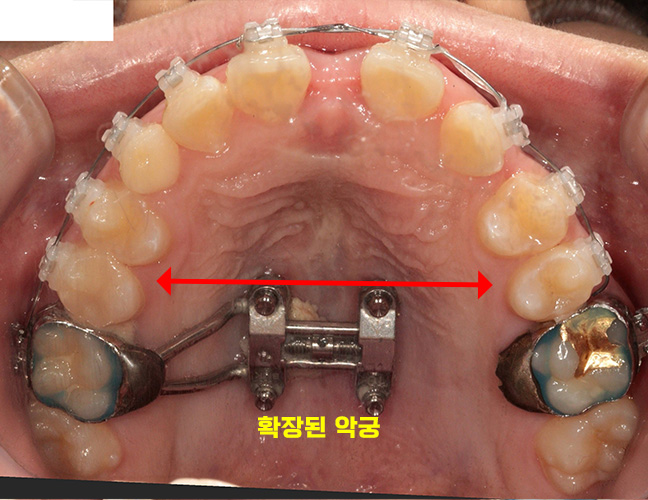

25.09.29

이후 만들어진 장치를

치아에 장착하여

확장하는 치료가

진행되었습니다.

이 과정은 좁은 악궁을 넓혀

송곳니가 정상적으로

자리를 잡을 수 있도록 도와주는

중요한 단계입니다.

25.10.13

2주 정도 지난 뒤,

확인을 해보았습니다.

좁았던 악궁이 확장되었으며

그만큼 치아 간격도 더 넓어져

공간이 확보되었습니다.

이제 송곳니가 자리를 잡을 수 있는

충분한 공간이 마련되었으며,

이후에는 매복되어있는 송곳니를

견인하고 정상적인 위치로

이동시키기로 하였습니다.